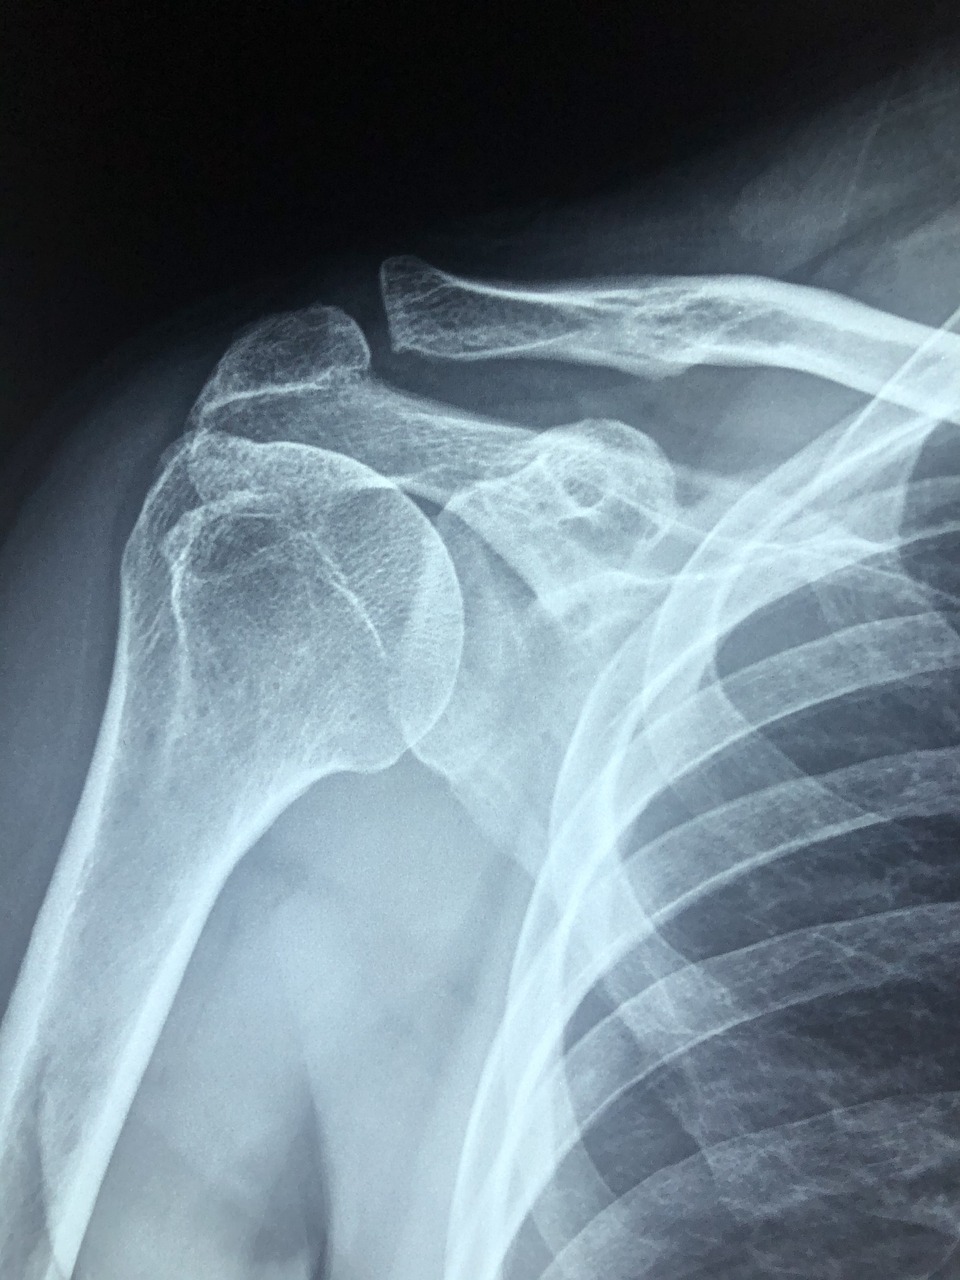

회전근개 수술 후 가장 궁금한 건 언제부터 어떻게 재활운동을 해야 하는지입니다. 너무 빨라도 무리가 되고, 너무 늦으면 어깨가 굳어버릴 수 있어요. 그래서 회전근개 재활운동의 순서와 주의사항은 매우 중요합니다.

어깨 회전근개 파열 후 효과적인 재활운동 방법과 꼭 지켜야 할 주의사항을 정리해 드릴게요.